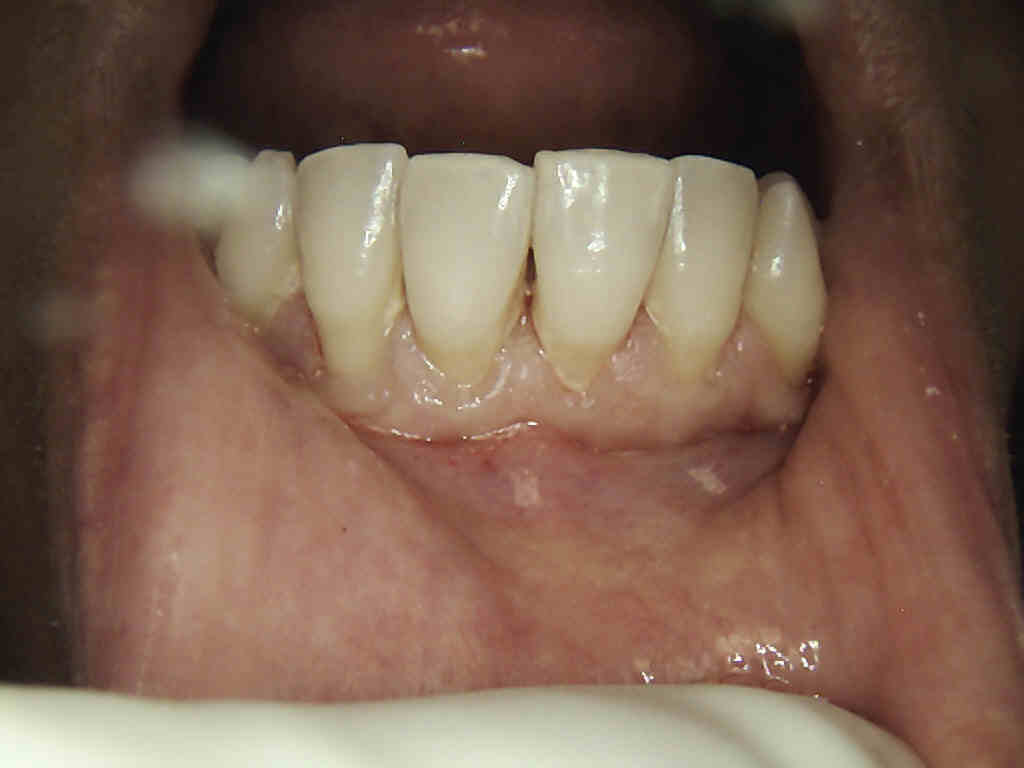

Unhealthy to Healthy Gums

Before

After

Note that these are preoperative recession cases that have minimal connective tissue.

The reason for the connective tissue graft is to ensure that the patient preserves bone and minimizes horizontal bone loss.